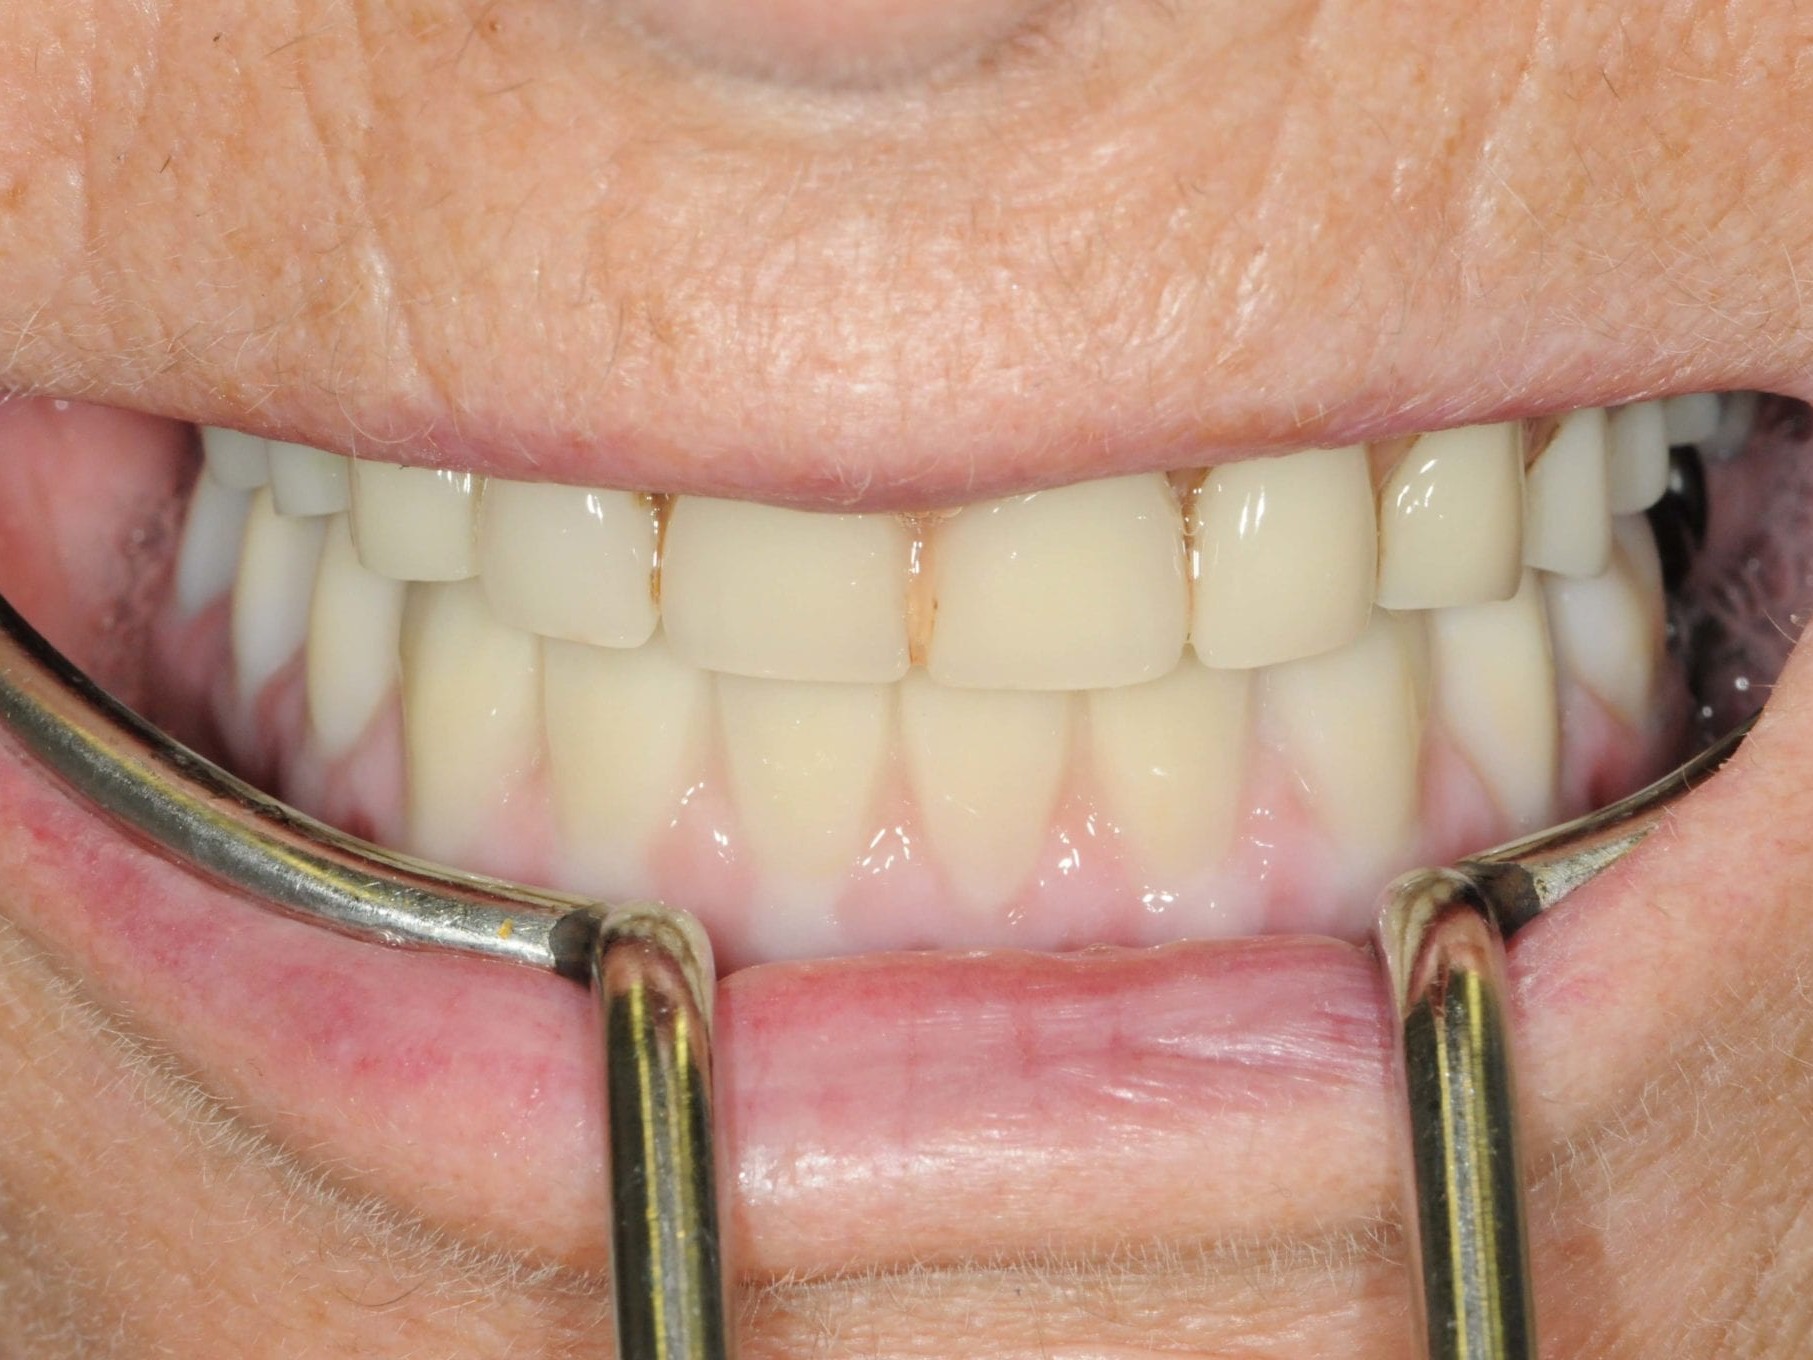

Für die Allgemeinanästhesie erfolgte zunächst die zusätzliche Gabe eines typischen Infiltrationsanästhetikums. Intravenös wurde unmittelbar präoperativ das Antibiotikum Clindamycin 600 mg gegeben. Abbildung 7 zeigt die klinische Ausgangssituation linksseitig. Nach der vorsichtigen Durchtrennung der Brückenkonstruktion (Abb. 8) jeweils vor der Krone auf den Blattimplantaten und Entfernung der nicht erhaltungswürdigen Zähne 44 bis 33 samt ihrer Überkronung (Abb. 9) wurde der Mukoperiostlappen vestibulär wie lingual passend zur erstellten Schablone präpariert und die Bohrschablone in ihrer finalen Lage eingebracht (Abb. 10). Zunächst erfolgte die Insertion der angulierten Implantate Ankylos ® C/X-Implantate (Durchmesser 3,5 mm) der Länge 14 mm in regio 034 (Abb. 11 und 12) und 044. Danach wurden in den Positionen 032 und 042 jeweils ein weiteres Ankylos ® C/X –A-Implantat mit gleicher Länge und Durchmesser inseriert (Abb. 13). Sämtliche entfernten Knochenpartikel und auch Bohrspäne wurden akribisch asserviert. In den Positionen 032 und 042 wurden Ankylos ® Balance Basisaufbauten C/ (GH 3,0 / Ø 5,5 mm, Kopfhöhe 2,4 mm) mit 15 N/cm eingeschraubt. Anschließend hat der Zahntechniker mittels der Ankylos ® Modellierhilfskappenfür den Balance Basisaufbau Retentionskappen hergestellt, die mit 25 N/cm eingebracht wurden (Abb. 14). Am Implantat regio 042 wurde der Knochen in Schalentechnik nach vestibulär aufgebaut (Abb. 15)⁹,¹⁰. Im nächsten Schritt haben wir die angulierten Ankylos ® Balance Basisaufbauten C (nicht indexierte Abutments) in Regio 034 und 044 (GH 3,0, A30 / Ø 4,2 mm, Kopfhöhe 1,3 mm) ausgerichtet und ihren spezifischen Vorgaben entsprechend eingebracht (Abb. 16). Nachdem sich alle erforderlichen prothetischen Implantatbauteile in situ befanden (Abb. 17), erfolgte die Überprüfung und geringfügige Anpassung des im Vorfeld digital erstellten Sofortprovisoriums. Im Anschluss wurden die leeren Alveolen und Knochendefekte mit dem gewonnenen autologen partikulären Material aufgefüllt. Dann erfolgte der typische Naht-Wund-Verschluss mit Einzelknopfnähten eines resorbierbaren Nahtmaterials (Abb. 18). Nachdem die Patientin aus der Vollnarkose erwacht war und ihre motorischen Fähigkeiten wiedererlangt hatte, wurde das Sofortprovisorium eingesetzt und in Okklusion gebracht. In dieser Position wurden die Retentionskappen über ein selbsthärtendes fluoreszierendes kaltpolymerisierendes Paste-Kartuschensystem fixiert. Anschließend erfolgte die extraorale Versäuberung des Interimszahnersatzes. Nach Refixierung des Sofortprovisoriums in der Mundhöhle (Abb. 19 und 20) und dem Verschluss der Schraubenkanäle mit Kunststoff erfolgte die radiologische Kontrolluntersuchung (Abb. 21).

Nach erneuter Überprüfung der implantatprothetischen Sofortversorgung auf sämtliche okklusalen und gelenkspezifischen Parameter erfolgte die Abformung im Ober- und Unterkiefer (Abb. 22). Da die Ankylos Balance-Basis Aufbauten intraoperativ bereits zum Zeitpunkt der Interimsversorgung definitiv eingesetzt wurden, erfolgte die Abformung auf Abutmentniveau mit einem Folienlöffel für präzise Implantatabformung. Um die visuelle Kontrolle über den Abformprozesses zu haben, kam ein transparentes Abformmaterial zur Anwendung. Zur präzisen Übertragung der Mundsituation auf das Modell ist entweder eine zweite Abformung mit einem entsprechenden laborgefertigten Kontrollschlüsssel oder eine direkte intraorale Verblockung der Ankylos Abformpfosten erforderlich¹¹. Bei der letztgenannten Variante werden die direkte Verblockung der Abformpfosten und die präzise Implantatabformung miteinander kombiniert (Abb. 23). Hierfür wird Zahnseide spannungsfrei mehrfach über Kreuz um die Abformpfosten geschlungen. Das hieraus entstehende Gerüst dient als Trägerplattform für das Autopolymerisat, das wir in Pinseltechnik appliziert haben. Um ein zügigeres Arbeiten am Patienten zu gewährleisten, kamen vorgefertigte Stangen (Ø 3 mm) aus rotem Modellierkunststoff zum Einsatz. Dieser Modellierkunststoff zeigt auch bei sehr dünnen Schichtstärken eine minimale Schrumpfung bei hoher Festigkeit sowie Stabilität. Das zeitversetzte Applizieren des Autopolymerisates gewährleistet die Spannungsfreiheit der Verblockung. Das Meistermodell wurde aus Klasse–IV-Superhartgips mit typischer Gingivamaske hergestellt. Bei weitspannigen Suprastrukturen lässt sich die höchste Genauigkeit mit einer verblockten Präzisionsabformung erreichen. Die durch das nach distal ausgedehnte prothetische Polygon bedingte Weitspannigkeit ist das Prinzip des SmartFix-Konzeptes. Nach der Modellherstellung erfolgte die anatomisch korrekte Übertragung der Schädel-Achs-Relation des Oberkiefers in den Artikulator mittels Gesichtsbogen. Zur Montage des Unterkiefers konnte in diesem Fall auf eine klassische Bissnahme verzichtet werden, da das computerdesignte und okklusal verschraubte Langzeitprovisorium während der Einheilphase vom Behandler feinjustiert wurde und somit die Bisshöhe und -lage zur Übertragung perfekt geeignet war. Hierfür wurde das Provisorium entnommen, so dass der Zahntechniker die Artikulation und die damit verbundene Individualisierung der Artikulatorenwerte in der Praxis vornehmen konnte. Im Labor erfolgte die komplette Digitalisierung des Falles. Der gesamte Workflow dieses Patientenfalles beruht auf dem Prinzip des Backward Plannings. Dem Team, bestehend aus einem implantatchirurgischen und einem implantatprothetischen Behandler sowie einem Zahntechniker, ist daran gelegen, sowohl chirurgisch als auch prothetisch vorhersagbare Ergebnisse zu generieren. Bei einer okklusal verschraubten Brücke ist es für den Zahntechniker vor Beginn der Arbeit wichtig, den späteren Austrittspunkt der Schraubenkanäle zu kennen und eine diagnostische Aufstellung in Form und Funktion anzufertigen. Nur so wird gewährleistet, dass das CAD/CAM gefertigte Gerüst die Verblendungen optimal unterstützt und die Schraubenkanäle ideale Durchtrittspunkte bekommen. Durch das im Vorfeld erstellte digitale Sofortprovisorium konnte die ästhetische Ausgangssituation der Patientin sowie die individuellen Okklusionsparameter bis hierhin fehlerfrei übernommen werden. Dieses Sofortprovisorium wurde mittels Alginat in situ abgeformt und nach der Modellherstellung digitalisiert. Zur Steigerung der Präzision wurde darüber hinaus ein klassisches diagnostisches Wax-Up erstellt, das den Verlauf der rot-weißen Ästhetik wiedergab. Diese Datensätze wurden dann mit den Scandaten des Meistermodells in einem CAD Programm gematcht (Abb. 24). Damit standen dem Zahntechniker alle benötigten Informationen zur Erarbeitung eines Designvorschlages für das anatomisch teilreduzierte Brückengerüst aus Zirkondioxid zur Verfügung. Die auf den Zehntelmillimeter genau festzulegende Reduktion des Gerüstes richtet sich nach der Indikation der Verblendung. Wie weiter oben bereits beschrieben, ist die Patientin im Oberkiefer mit einer herausnehmbaren Kunststofftotalprothese versorgt. Aus Sicht des Behandlungsteams war dadurch eine keramische Verblendung des Unterkiefers möglich. Aus Stabilitätsgründen entschied sich das Team für eine Versorgung aus monolithischem Zirkondioxid, das zur Steigerung der Ästhetik von 033 bis 043 vestibulär verblendet wurde (Abb. 25). Die Verwendung von monolithischem Zirkon in Verbindung mit einer keramischen Teilverblendung gewährleistet neben der notwendigen Ästhetik und Stabilität zwei weitere Vorteile. Auf der einen Seite zählt Zirkondioxid in der Zahnheilkunde zu den Materialien mit der höchsten Biokompatibilität und zum anderen werden die auftretenden Kaukräfte gerade in Verbindung mit der Versorgung im Oberkiefer gleichmäßiger auf das Implantat und den Knochen verteilt. Gerade bei implantologischen Oberkiefer- und Unterkieferversorgungen ist dieser „Stoßdämpfer–Effekt“ für den Langzeiterfolg wichtig. Im vorliegenden Fall wurde die okklusal verschraubte Brücke mit einem Sintergerüst versehen und mit einer fünfachsigen Fräsmaschine im Labor aus einem Zirkonblock gefräst. Bevor das Gerüst mit einem speziell entwickelten Langzeitprogramm gesintert wurde, erfolgte die individuelle Einfärbung des Zirkondioxides mit Color Liquids. Die anschließende vestibuläre Verblendung der Zähne und des Zahnfleisches wurde unter Zuhilfenahme der diagnostischen Aufstellung mit Verblendkeramik angefertigt. Hierbei wurde besonderer Wert auf die naturgetreue Nachbildung der Rot-WeißÄsthetik und eine gute Hygienefähigkeit geachtet. Die gefertigte Arbeit wurde mit einem dafür zugelassenen Kleber auf die Ankylos Stegkappen (für Balance Basisaufbau schmal, aus Permador® PDF, Dentsply Implants) verklebt, die zuvor auf dem Meistermodel aufgeschraubt worden waren. In Übereinstimmung mit den als Sheffield-Test¹² bekannten Kriterien der University of Sheffield, GB, ermöglicht dieser Fertigungsprozess in Kombination mit der verblockten Abdrucknahme einen präzisen und somit spannungsfreien Sitz der Brücke – sowohl auf dem Meistermodell als auch im Munde des Patienten (Abb. 26 bis 28). Nach der zahntechnischen Fertigstellung der Unterkieferbrücke wurde diese intraoral inkorporiert (Abb. 29 und 30). Die Ankylos Implantatschrauben wurden mit 25 Ncm angezogen. Wichtig ist, dass stets das Originalequipment des Herstellers oder ein elektronisch kalibrierter Schraubendreher verwendet wird. Die Schraubenkamine wurden mit einem bakteriendichten, formstabilen lichthärtenden Füllungsmaterial verschlossen. Nach 6 Wochen wurde ein abschließendes OPG erstellt (Abb. 31).